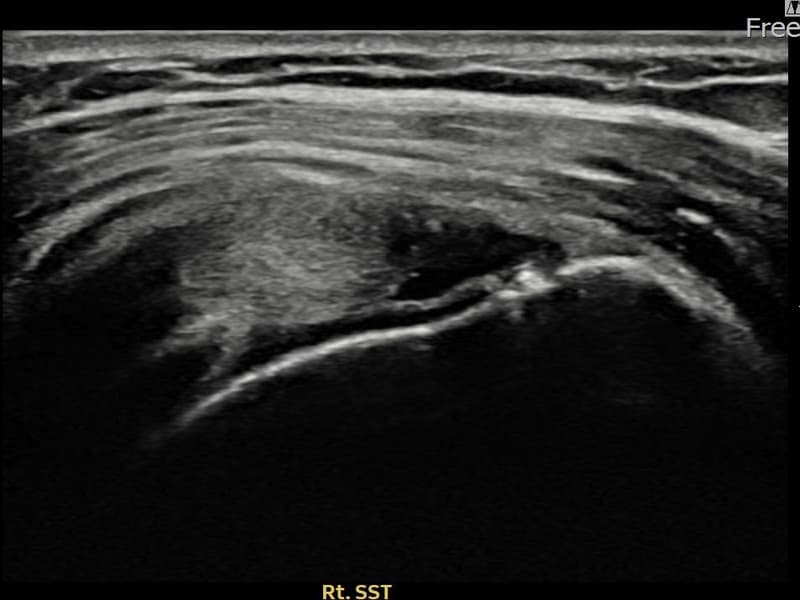

术前

术前超声确认右侧 冈上肌腱 关节面侧部分撕裂,右侧冈上肌腱回声不连续伴肌腱缺损(12mm × 4mm (肌腱厚度约48%缺损))。术后超声显示撕裂部位充满再生组织,肌腱连续性恢复,回声模式正常化。